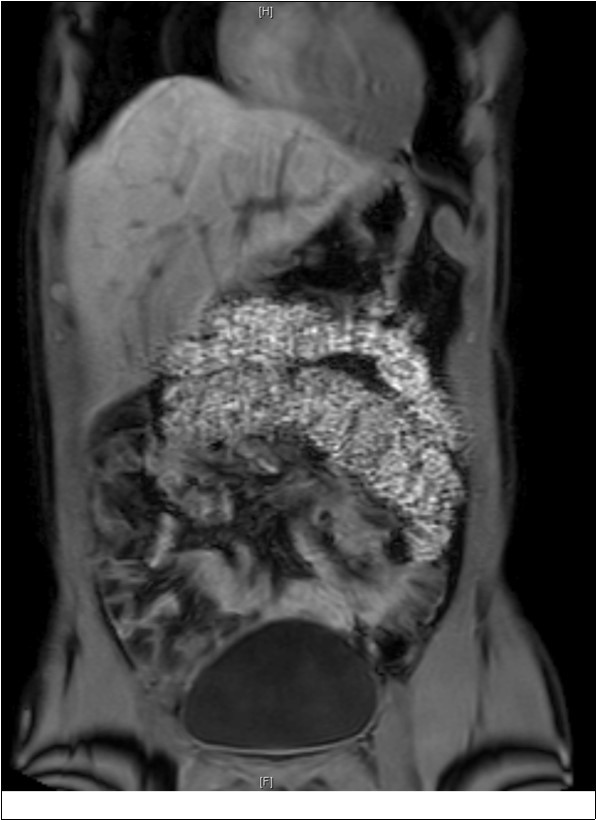

As part of the workup, an enterography magnetic resonance imaging (MRI) was done and showed non-rotation with the small bowel and colon in the right and left abdomen, respectively (Figure 1). A complementary upper gastrointestinal series (UGIS) was requested and the duodenal jejunal junction was abnormally located confirming malrotation (Figure 2).

Figure 1.MRI showing non rotation